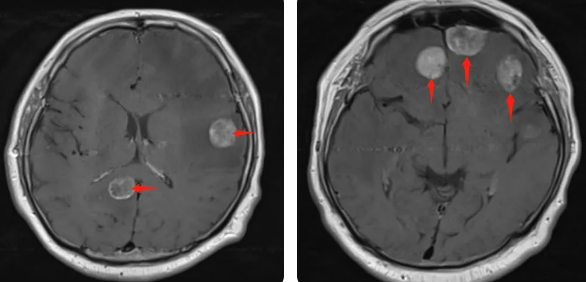

無(wú)獨(dú)有偶,60歲的左肺癌患者石先生,在外院接受了手術(shù)治療,結(jié)果術(shù)后10月出現(xiàn)腫瘤腦轉(zhuǎn)移,頭部增強(qiáng)MRI顯示:顱內(nèi)多發(fā)占位性病變伴水腫,接二連三的重?fù)糇屖壬霈F(xiàn)表情淡漠,沉默寡言,絕食等抑郁癥狀,VMAT放療技術(shù)與心理疏導(dǎo)雙管齊下,3周的治療后顱內(nèi)轉(zhuǎn)移病灶顯著縮小,部分甚至消失,困擾石先生的頭痛、頭暈癥狀也不復(fù)存在,石先生重拾對(duì)生活的希望,也對(duì)未來(lái)的治療充滿(mǎn)信心。